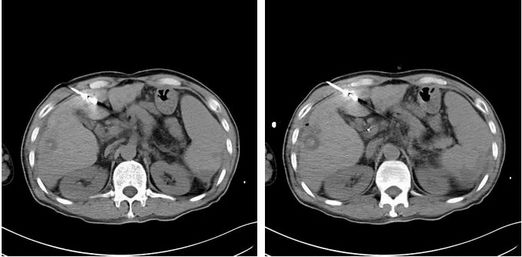

12月初,张叔再次来到医院就诊。经CT检查提示肝硬化,脾大,腹水,门脉高压,侧支循环开放,食管胃底静脉曲张。门脉主干及左叶、右前叶分支见充盈缺损,肝左叶近肝裂区似见稍低密度结节,增强不均匀稍强化,边缘不清,门静脉左支、主干及部分右支增粗,腔内充盈缺损,增强中度强化,肝门区及腹主动脉旁淋巴结增多、部分增大,考虑肝左叶肿瘤性病变。综合患者各项生理指标,为控制肿瘤病灶的进一步增大,以牛立志教授为首的专家团队建议他进行微波消融治疗。因为张叔的血小板只有5万多,而氩氦刀冷冻消融会消耗血小板,这种情况出血风险比较大,而微波消融对血小板影响小,对肝硬化失代偿的患者来讲可以争取更多的抗肿瘤治疗机会。

12月14日张叔在B超加CT引导下行肝脏肿瘤微波消融治疗,过程顺利,术中消融区域定位准确,消融范围满意,术后未诉不适,生命体征平稳,术后恢复良好,并且在术后第三天出院回家。